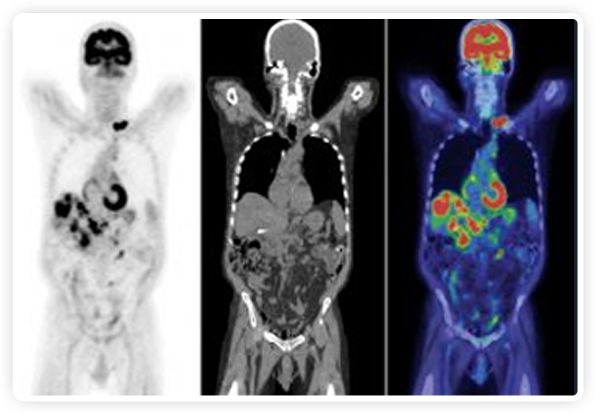

提起放療設備的引導系統,大家通常會想到結構性成像的CT或核磁。但你有沒有想過用功能性成像來引導放療呢?美國的一家醫療器械公司從2011年就致力于研究開發用PET提供生物學指導放射治療的設備BgRT。BgRT能實時利用癌癥的生物學特征作為信號指導治療全身腫瘤。

正電子發射斷層掃描(PET)是癌癥檢測中已建立的成像標準,與其他成像方式相比,PET能提供高靈敏度和特異性的圖像。

到目前為止,放射腫瘤學中(使用的圖像主要是結構性的,而PET圖像可以提供生物學信息。通過使用注射示蹤劑,例如18-FDG,PET可以描繪腫瘤的代謝活性,使其“點亮”。(FDG是用于可視化癌癥代謝的最廣泛使用的示蹤劑。與正常組織相比,腫瘤細胞保留更高水平的FDG。)不同的PET示蹤劑可以識別腫瘤的不同生物學特征,例如特定生物標志物抗原(例如,PSMA)或甚至探測免疫系統本身(例如,PDL1表達或活化的T細胞)。

RefleXion將PET成像與立體定向放射治療相結合。在注射示蹤劑后,RefleXion的技術基于示蹤劑信號實時地在一個或多個目標上引導治療性X射線。使用這種專有方法,RefleXion的平臺有可能比現有系統向癌癥病變提供更高劑量的輻射,并改善周圍健康組織的保護。

為了避免PET長圖像采集時間,RefleXion開發了一項專利技術使用重合的PET光子對來指導放射治療束,因為實時檢測發射的光子,為生物指導提供了一種時間有效的方法。